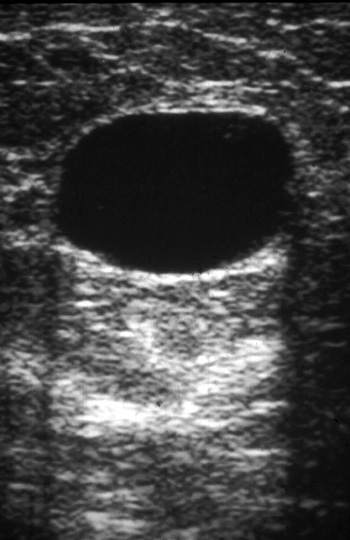

يكشف فحص الماموجرام عن وجود آفة مشبوهة بالسرطان في الثدي الأيسر. لا توجد كتلة واضحة. كيف يمكنك المضي قدما؟

إجابة

الخزعة الأساسية للتوجيه المجسم أو الموجات فوق الصوتية. أو

استئصال خزعة

يقوم أخصائي الأشعة بإجراء عملية توطين الإبرة أولاً.

يتم ضغط الثدي بحامل له إحداثيات على…